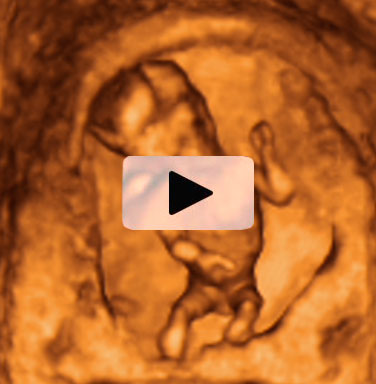

Ecografía Embarazo 2D y 3D Semana 12 - CRIBADO DEL PRIMER TRIMESTRE

Ecografía Embarazo 4D Semana 12 - CRIBADO DEL PRIMER TRIMESTRE